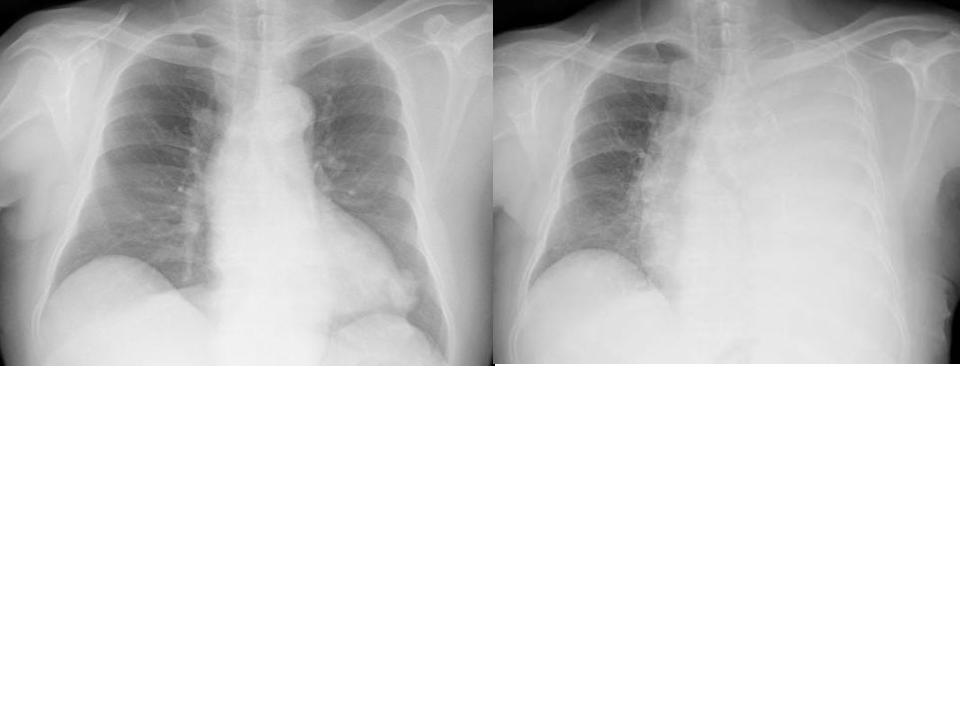

こちらを見て下さい。

わかりにくいかもしれませんが、このあたり。

気管が追いにくい、無くなっているようにも見えます。

CTで見ると…

気管狭窄ですね。こういう所見もレントゲンで捉えることができるのです。